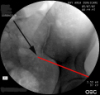

Circle at tip of needle is the facet arthrogram. Note inferior dye extravasation.